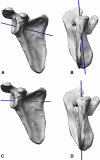

Background: The reverse total shoulder arthroplasty was introduced to treat the rotator cuff-deficient shoulder. Since its introduction, an improved understanding of the biomechanics of rotator cuff deficiency and reverse shoulder arthroplasty has facilitated the development of modern reverse arthroplasty designs.

Results: Various implant design factors as well as various surgical implantation techniques affect stability of reverse shoulder arthroplasty and patient function. To understand the implications of individual design factors, one must understand the function of the normal and the cuff-deficient shoulder and coalesce this understanding with the pathology presented by each patient to choose the proper surgical technique for reconstruction.